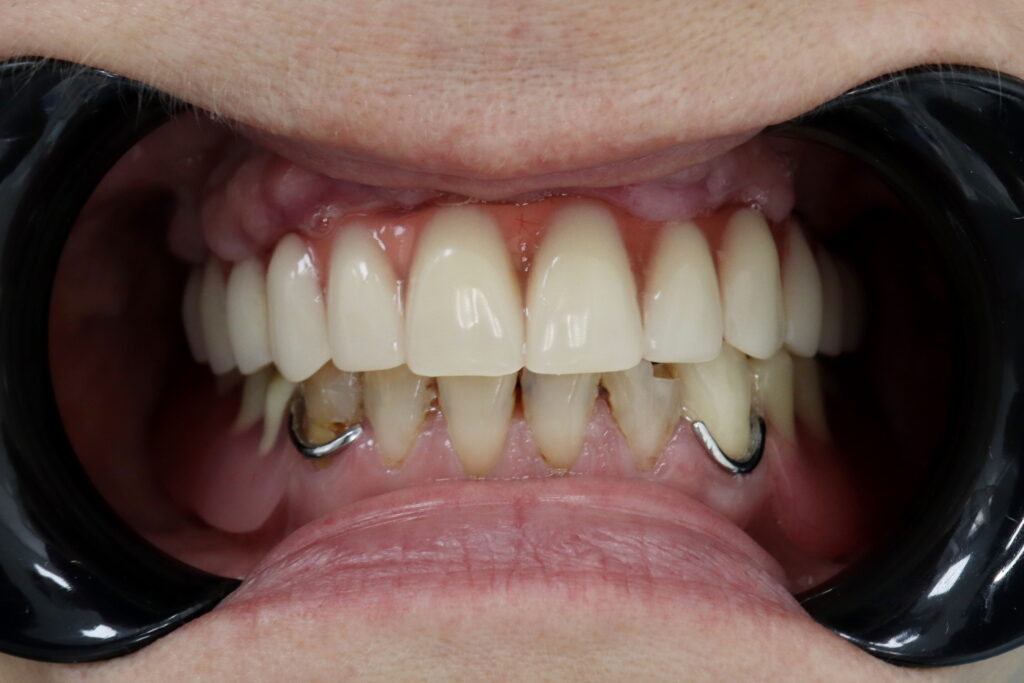

Результаты

Результат имплантации